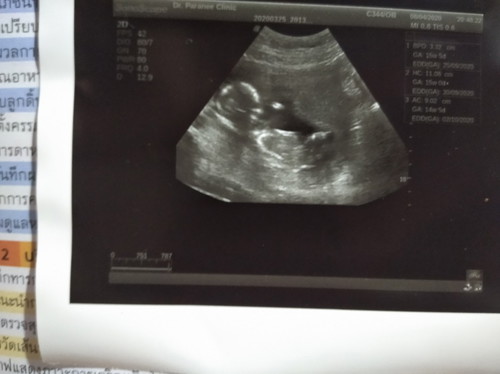

ตั้งครรภ์

15w ขอดูของคุณแม่คนไหนคลอดเดือนกันยายนมั่งค่ะ